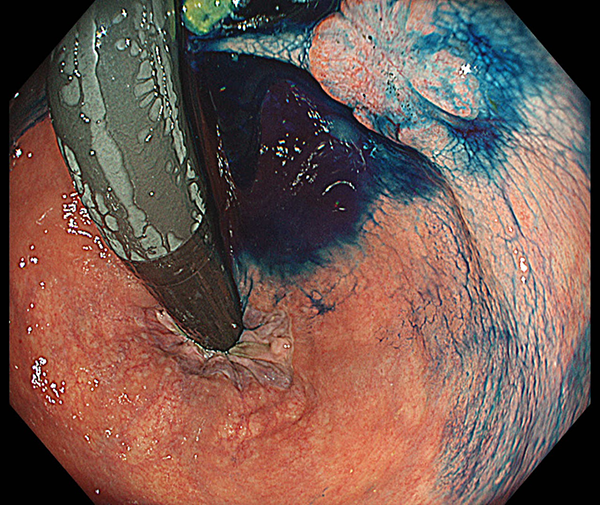

ロボット支援下手術では、高画質3D立体的映像のもとで手術を行うため、腹腔鏡下手術の欠点であった遠近感覚が改善されます。また、使用する鉗子類は人間の手よりも広い可動域を持ち、複雑かつ繊細な動きが可能なため、術者の指先の動きを明確に再現することができます。なおかつ手振れ防止機能も有するため、従来の腹腔鏡下手術よりもさらに正確な手術を行うことが可能です。さらに、ダビンチXiサージカルシステムに内蔵された蛍光内視鏡の赤外線蛍光波長で臓器を観察すると、血液の流れ具合を確認することができます(図8)。この機能を使って血流が豊富な部分で腸管をつなぎ合わせると縫合不全の発生率が低下することが報告されており、人工肛門を回避しやすくなると考えています。